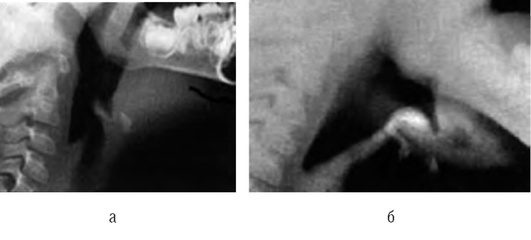

Рентгенография не относится к стандартным методам исследования, однако ее следует проводить при отсутствии ответа на лечение для исключения пневмоторакса, сопутствующих заболеваний легких. В приступном периоде БА у детей раннего возраста на рентгенограмме грудной клетки отмечают резкое эмфизематозное вздутие легких, горизонтальное положение ребер, широкие межреберные промежутки, усиление сосудистого рисунка, расширение легочных корней. Во время приступа БА преимущественно субсегментарные ателектазы, которые обычно быстро расправляются, выявляют у 6-7% больных (рис. 3-6).

image

Рис. 3-6. Рентгенограмма грудной клетки: ателектаз верхней доли правого легкого во время приступа бронхиальной астмы